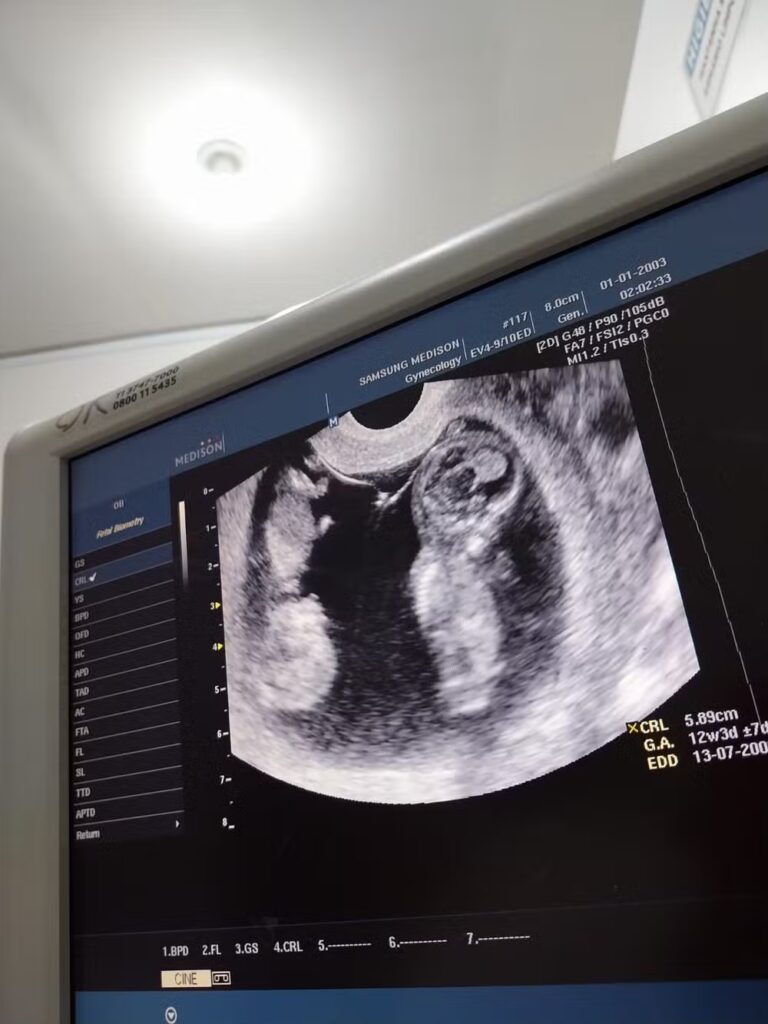

“Ela pediu ultrassom e, após o exame, ela disse que se os bebês dessem mais de 500 gramas, eles sobreviveriam, só iriam ficar na incubadora, na UTI [Unidade de Terapia Intensiva] neonatal. Até então, estava ciente disso, estava feliz, apesar do medo, mas aliviada, porque eu sabia que ia ter acompanhamento”, explica.

Após a morte dos filhos, Elizângela narra que não consegue dormir e que o sonhos de ter os filhos gêmeos nos braços a atormenta a todo momento. “Você sabe o que é você se preparar para aquela gestação inteira, os cuidados que eu tive, o tanto de ultrassom que eu fiz acompanhando eles, o tanto de consulta pré-natal, e vê que seus filhos escapuliram de você, sem ter uma explicação?”, lamenta.